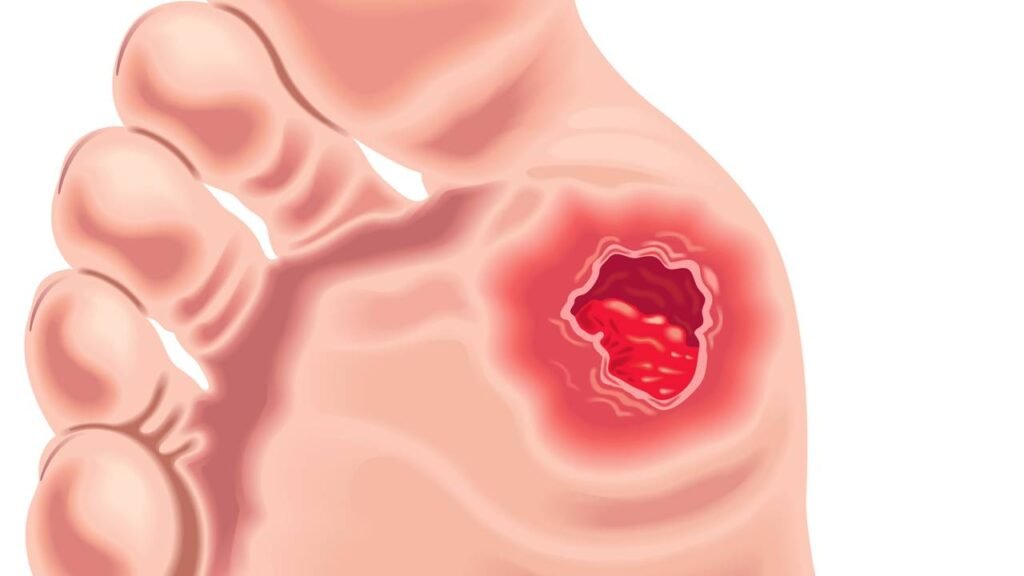

As lesões nos pés causadas pelo diabetes representam uma das complicações mais sérias enfrentadas por indivíduos com a doença. Essas alterações, conhecidas como “Pé Diabético“, ocorrem devido a alterações nos nervos e na circulação, frequentemente acompanhadas de infecções. Com mais de 20 milhões de brasileiros vivendo com diabetes, conforme dados do Ministério da Saúde, o risco de complicações cardiovasculares, incluindo problemas vasculares nos pés, é significativo.

A desregulação da glicose no sangue está diretamente associada a essas complicações. Conforme explica o cirurgião vascular Dr. Guilherme Yazbek, membro da Sociedade Brasileira de Angiologia e de Cirurgia Vascular, um controle glicêmico inadequado pode levar a alterações nos membros inferiores, como neuropatia periférica e piora da circulação, aumentando a vulnerabilidade a infecções e feridas graves. Estudos, como o publicado no Journal of Wound Care, mostram que até 30% dos indivíduos em populações vulneráveis no Brasil apresentam úlceras nos pés, sendo que cerca de 45% já passaram por amputações.

A identificação precoce de qualquer sinal de complicação nos pés, como dor, dormência ou feridas persistentes, é fundamental. Um diagnóstico rápido maximiza as chances de tratamento eficaz e diminui significativamente o risco de amputações. Portanto, a avaliação vascular imediata ao notar qualquer mudança é crucial.